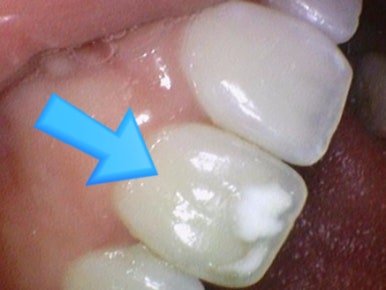

![[서울 광화문/남대문] 화이트스팟 레진으로 치료케이스, 비용안내 등등 / 반점치, 반상치 관련 이미지 2](https://pub-9f2bb3498faf4d1d8714b41df24753e3.r2.dev/content/clinics/archive/rseeanjxfu/naver_blog/yonseiyegam/assets/by_hash/deb79ce2fbd395a84fa86c94064d8107b641c3cc775a56c81630ecb6fa391fef.jpg)

화이트스팟 치료 전후

위의 환자분은 화이트스팟 치료를 원하셔서 진행하였고

내원 30분 정도만에 화이트스팟을 잘 치료하셔서 일주일 후에 오셨을 때 만족한다고 말씀하셨습니다.